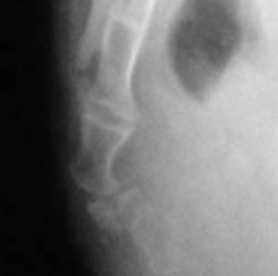

fracture du coccyx

fracture du sacrum (flèche)

arthrite micro-cristalline (radiographie standard)

Les fractures coccygiennes sont rarissimes (deux cas pour mille dans notre expérience, où seule la première pièce osseuse était concernée). Ceci se comprend car le point faible du coccyx est l’articulation sacro ou inter-coccygienne et non l’os lui-même. La lésion traumatique par excellence est donc la luxation. En revanche, les fractures de la partie inférieure du sacrum sont un peu plus fréquentes (1% de nos cas). Cette fréquence est probablement inférieure à la réalité, car nous voyons surtout des patients chroniques. Or, les fractures ne sont responsables que de coccygodynies aiguës, puisqu’elles guérissent spontanément dans un délai de trois à quatre semaines. Nous n’avons jamais observé de pseudarthrose.

La présence d’une petite calcification arrondie dans un disque est parfois observée. Elle n’a guère de valeur indicative (mais nous n’avons pas étudié spécifiquement cette question). En revanche, nous avons observé cinq cas d’arthrite micro-cristalline (probablement de l’hydroxy-apatite), soit une fréquence de 0.5%. Le tableau clinique est celui d’une douleur très intense, d’apparition brusque et spontanée, permanente, rendant impossible toute station assise. Elle cède à un traitement anti inflammatoire stéroïdien oral de quelques jours.